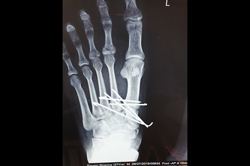

Metarsals with dislocations Lisfranc